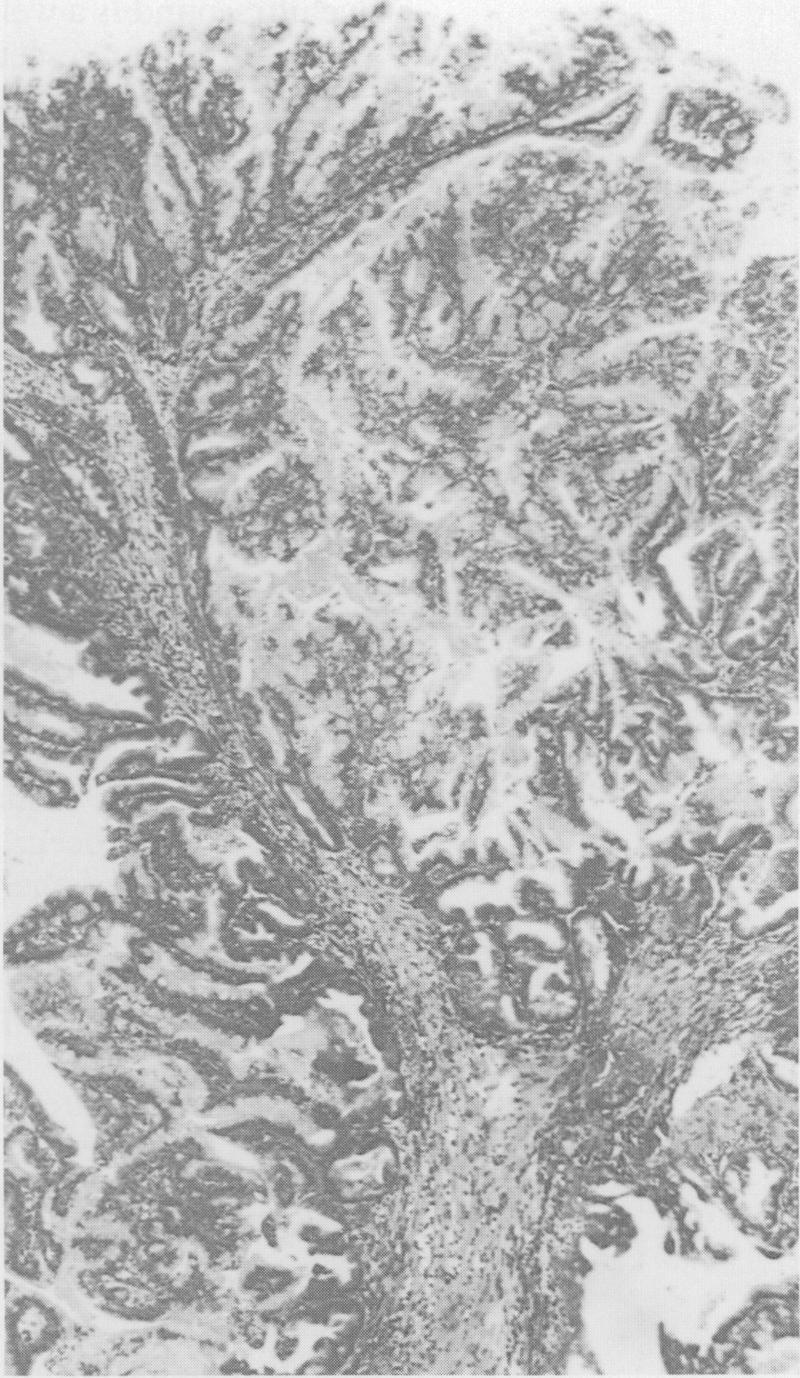

A case of villous adenoma of the common hepatic duct causing obstructive jaundice, where the diagnosis was made by ultrasound guided percutaneous biopsy is reported. At surgery ultrasonography was used to define the extent and operability of the tumour.

报告了一例肝总管绒毛状腺瘤导致梗阻性黄疸的病例,该病例通过超声引导下经皮活检作出诊断。手术时,超声检查用于确定肿瘤的范围和可切除性。